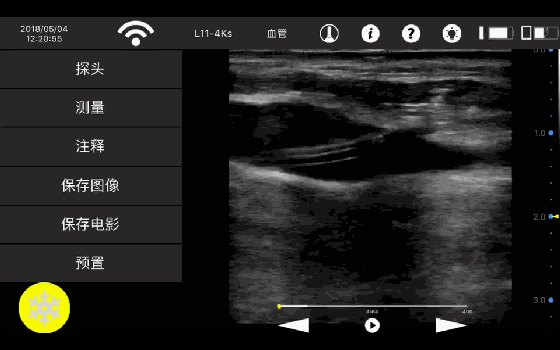

• 线阵

甲状腺

血管

神经

肌骨等